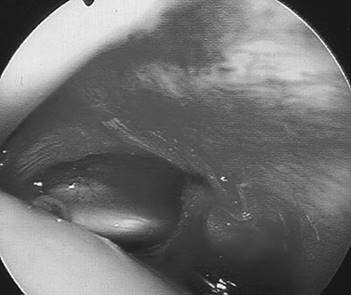

What is this?

This is a clinical photograph of a grossly deformed foot and ankle.

Charcot arthropathy is a severe destructive arthropathy which can occur in any patient with a sensory disturbance. Over 90 % of cases in the UK are related to diabetic neuropathy. (It occurs in 1 % of diabetics who have had the disease for 12 years.) The other causes can be thought of along the course of the sensory neurological system from peripheral to central: